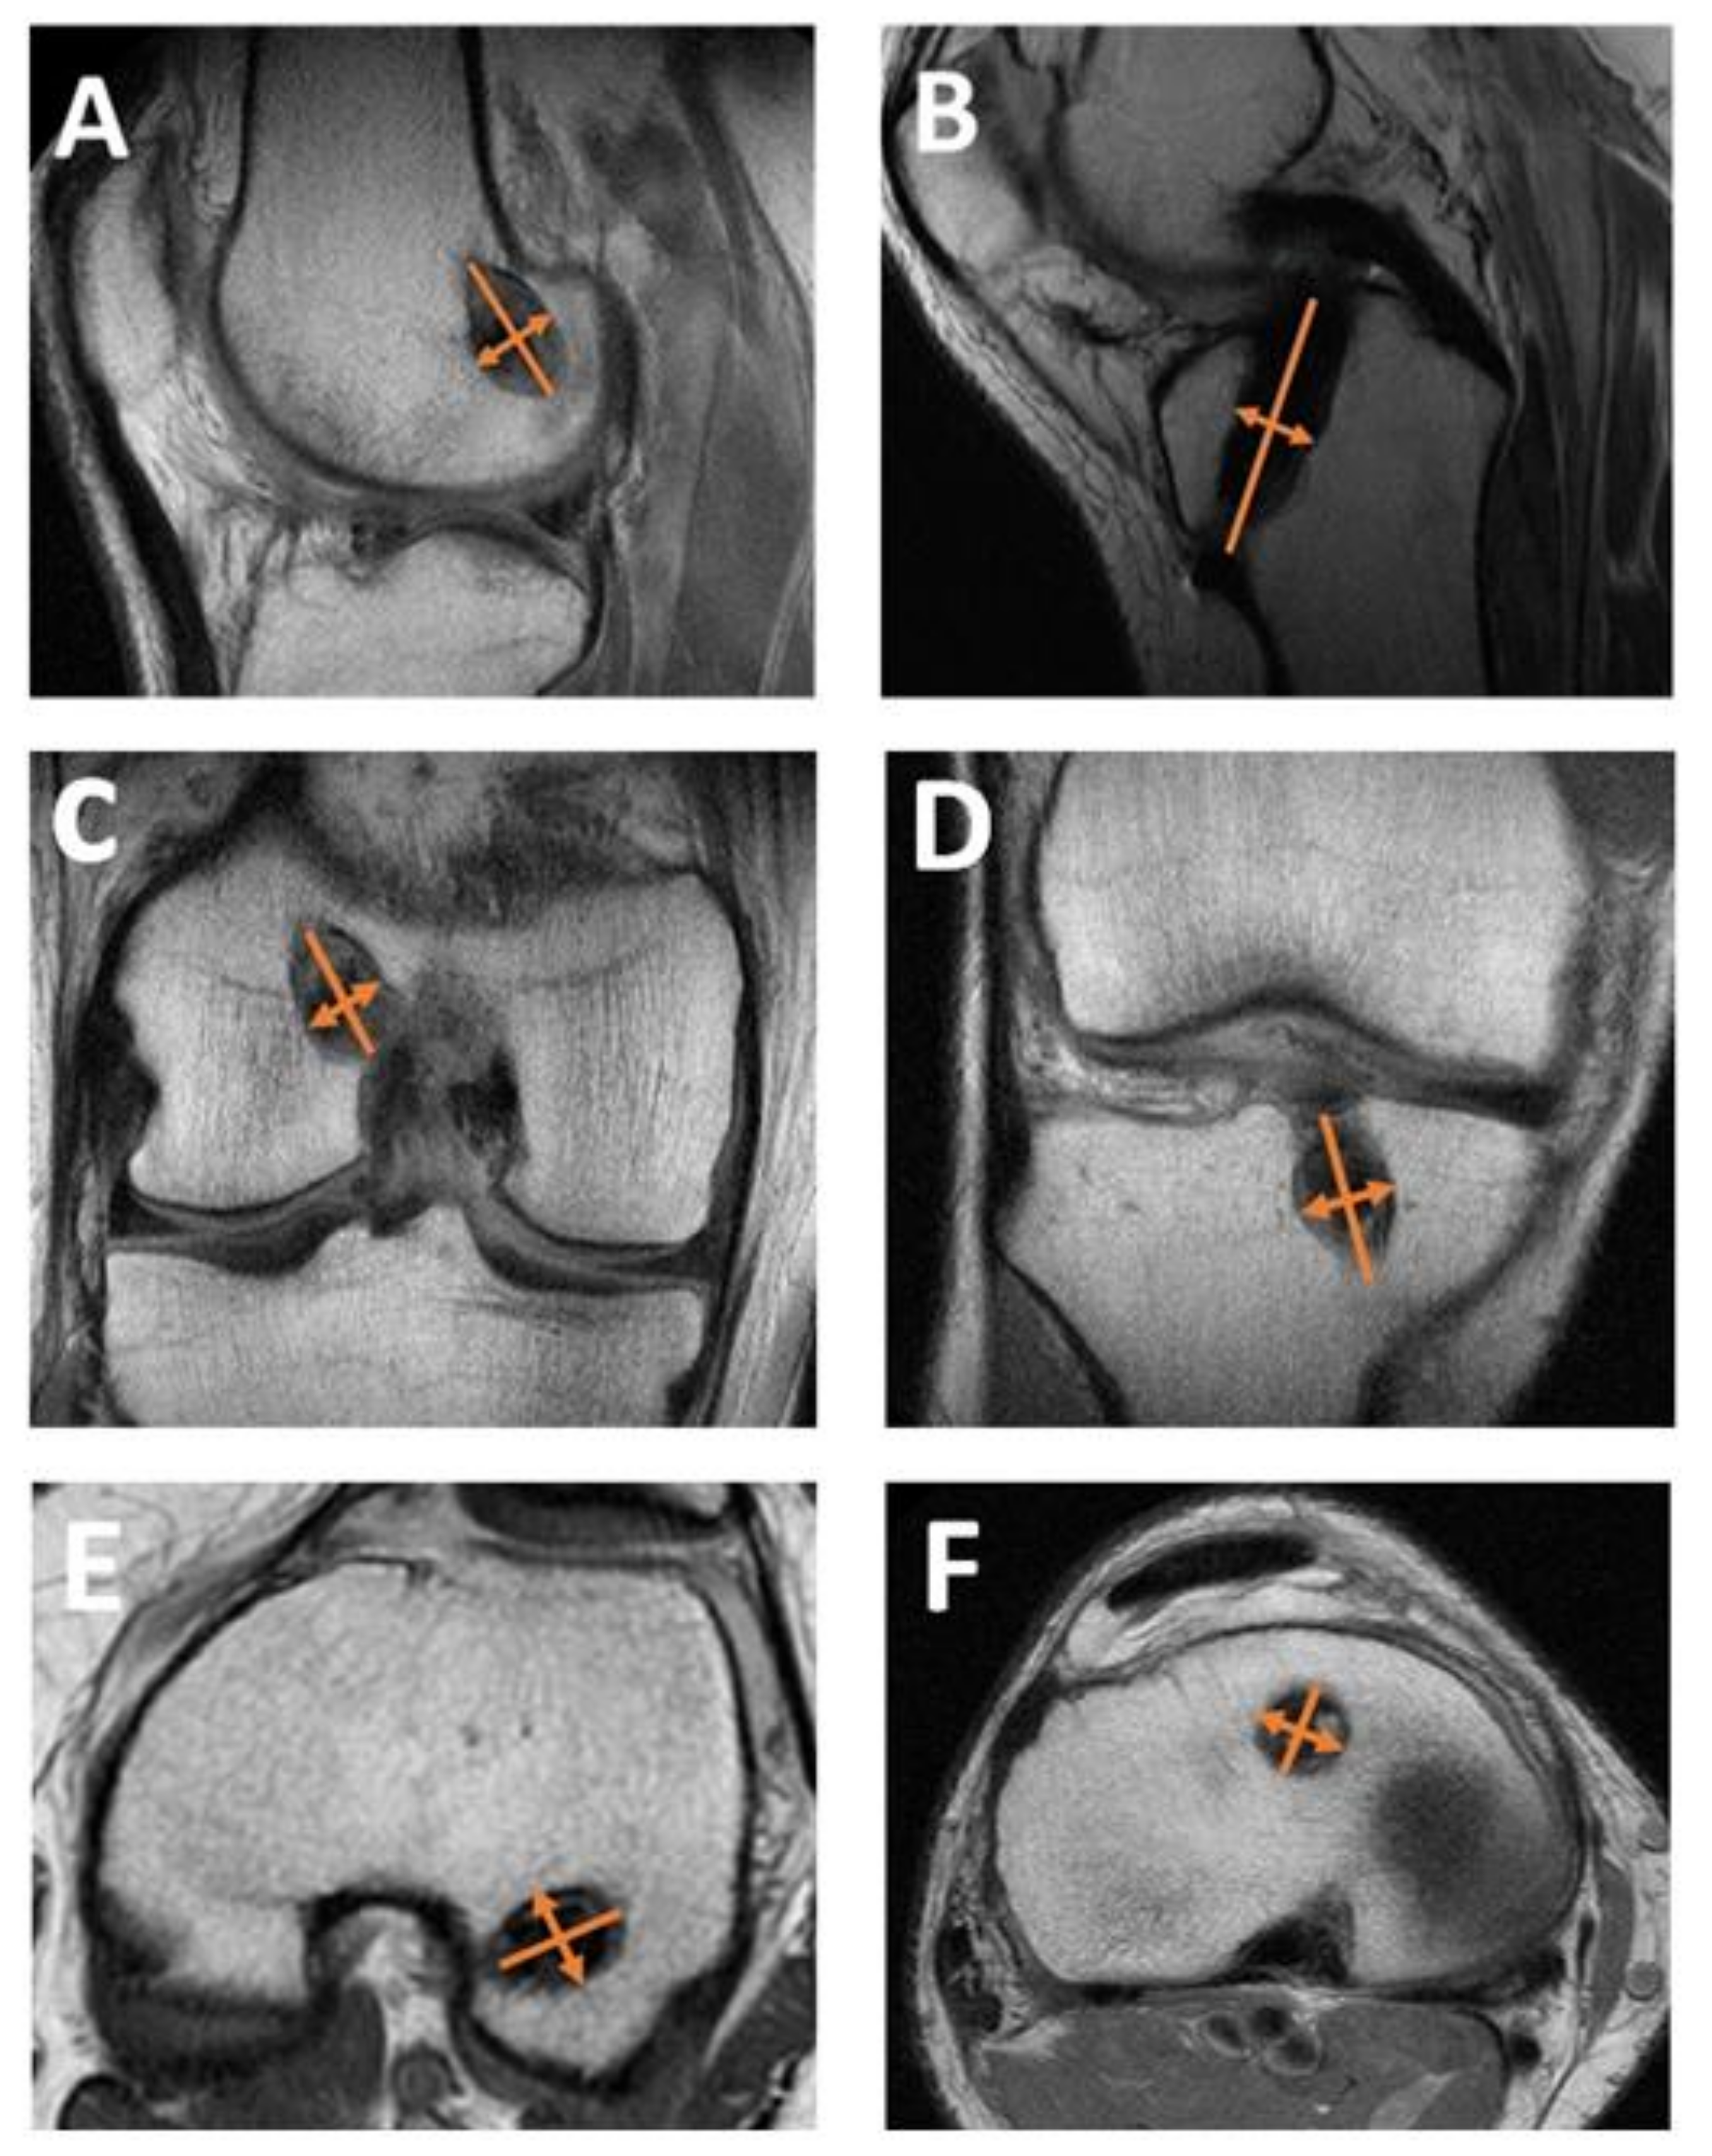

2.5. Measurement of Tunnel Widening

2.6. Measurement of Graft Maturation